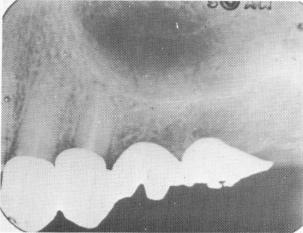

model the completed fixed denture was constructed (Fig. 15-55). The prosthesis contained the two veneer crowns and their acrylic facings. Distal to the second bicuspid crown and fixed to it was a scalloped template with a few protruding vertical pin heads (Fig. 15-56). The superstructure was also prefabricated. For this case, it consisted of two molar crowns cast in one piece, which fit exactly over the template (Fig. 15-57).

Fig. 15-57. The two-unit molar superstructure fits exactly over the underlying template.

1 Two-unit molar superstructure fit over pin implant template